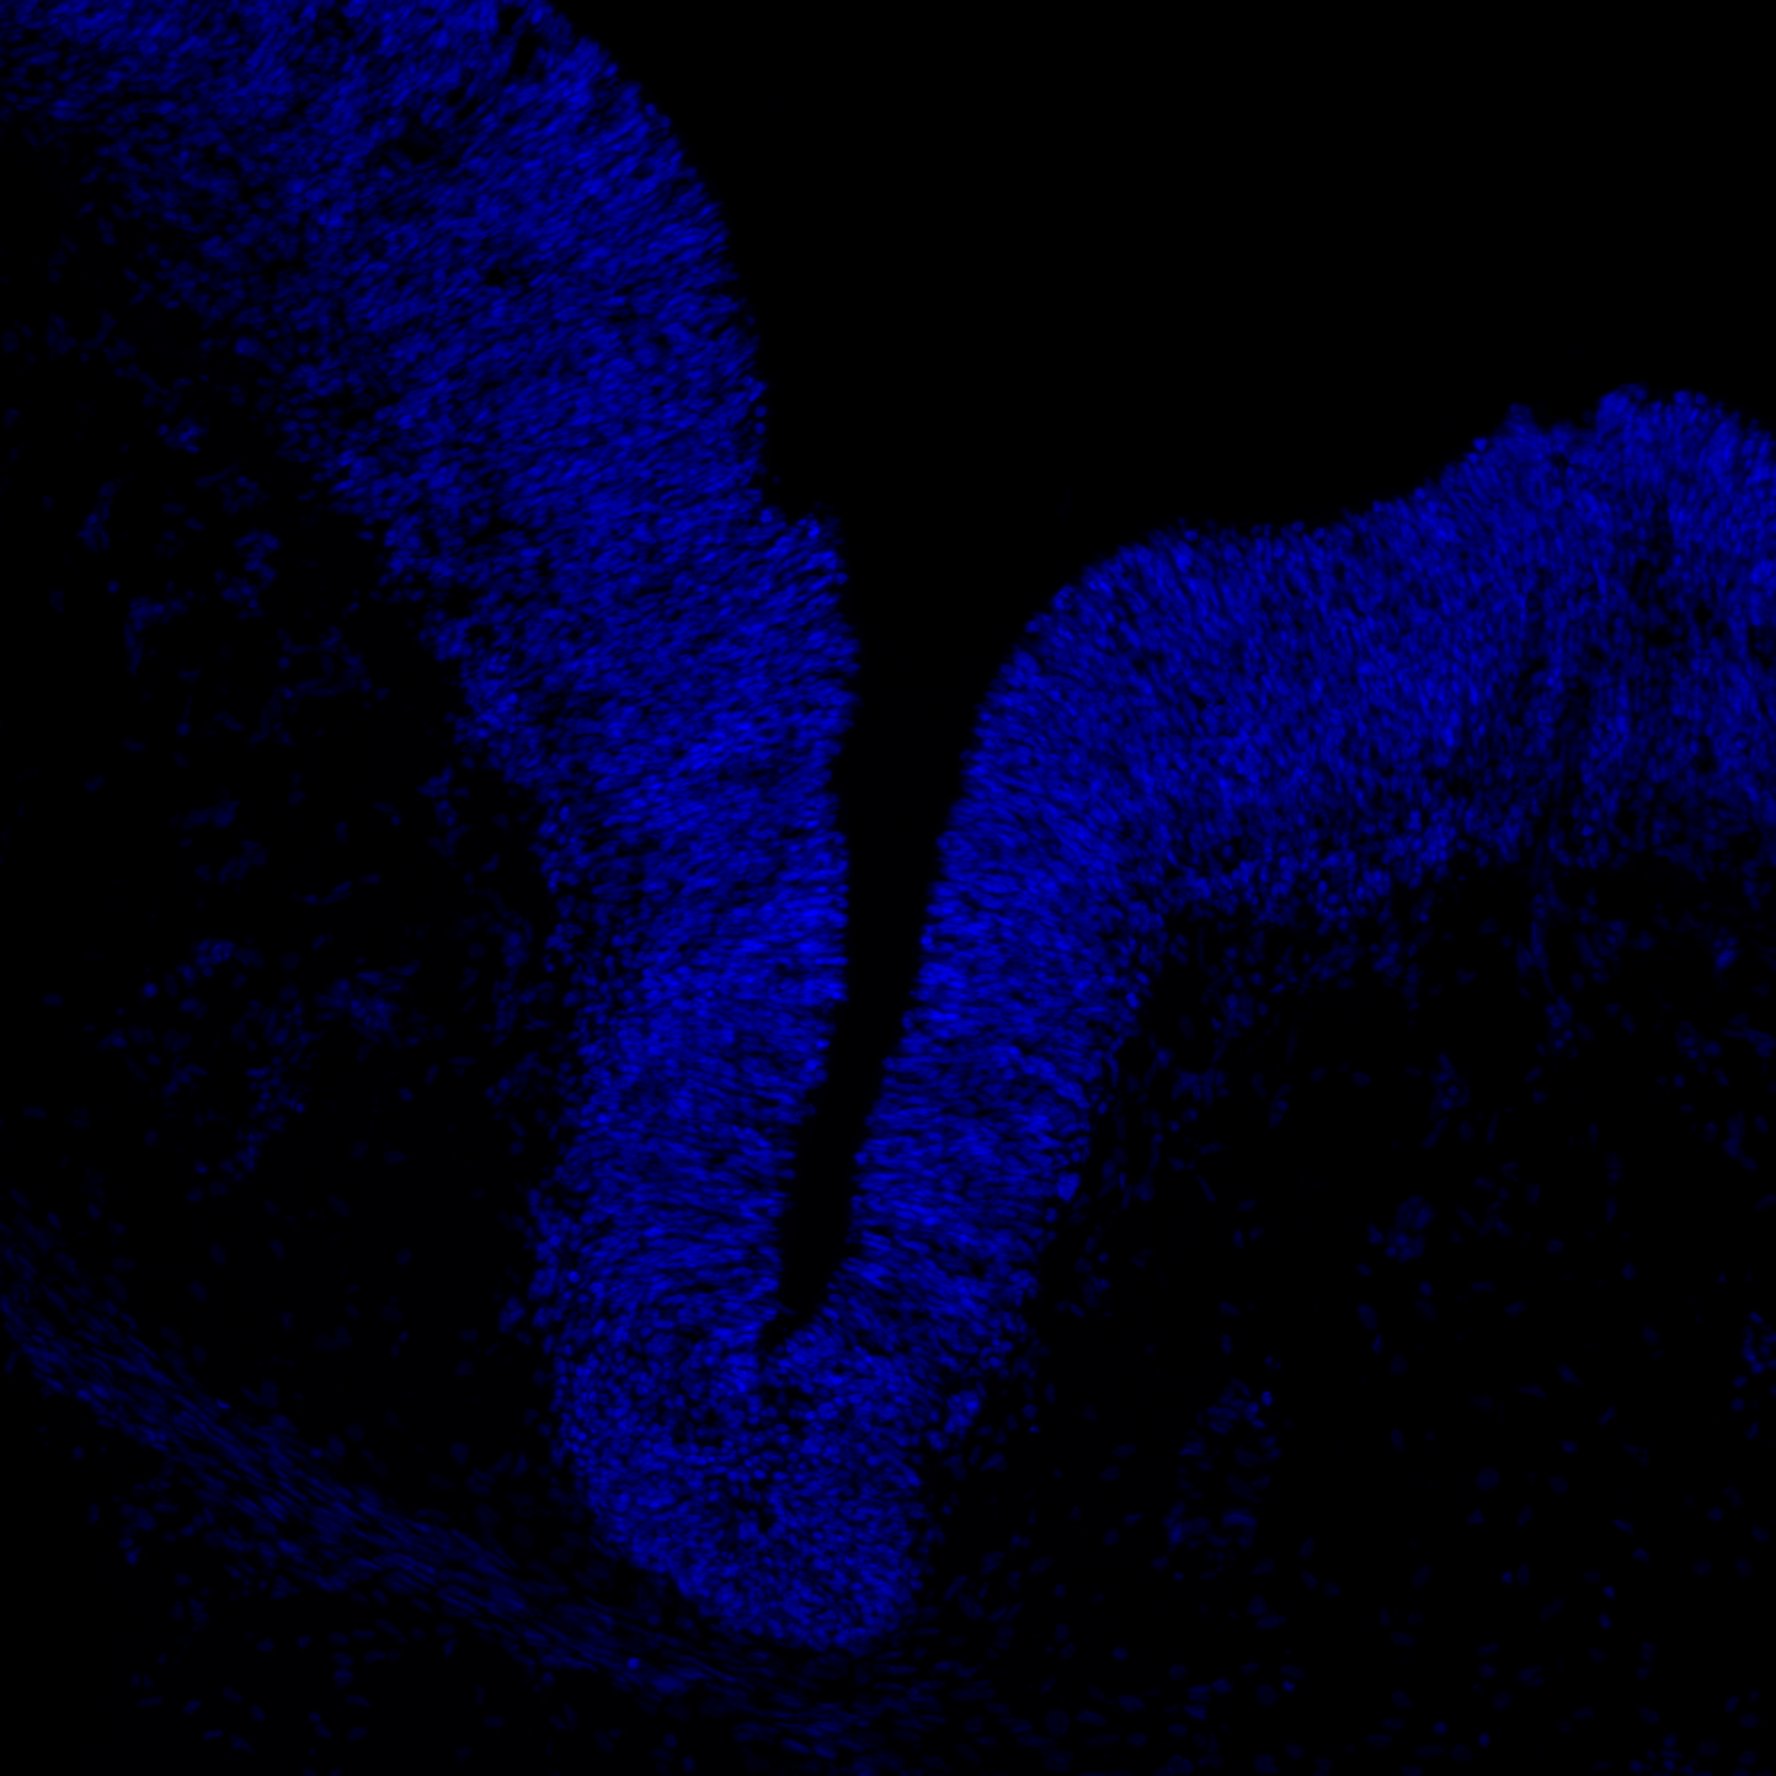

DAPI

7PCW human midbrain